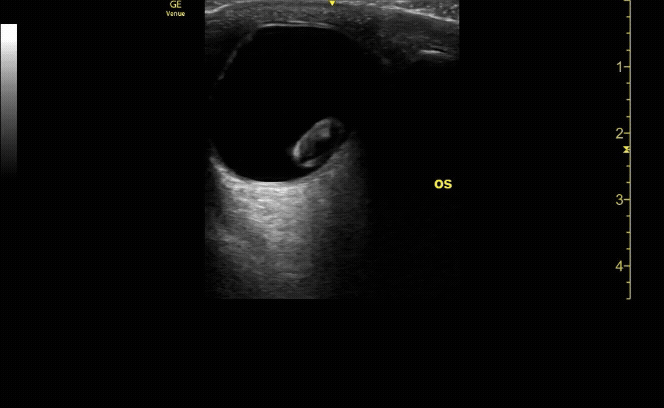

Measure the optic nerve sheath diameter (ONSD) 3mm from the back of the eye. The ONSD should measure <5mm across.

c/o John Elue, MD